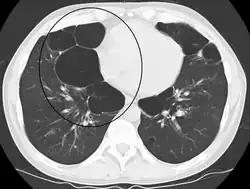

Axial CT image of the lung of a person with end-stage bullous emphysema -

Very severe emphysema with lung cancer on the left (CT scan)